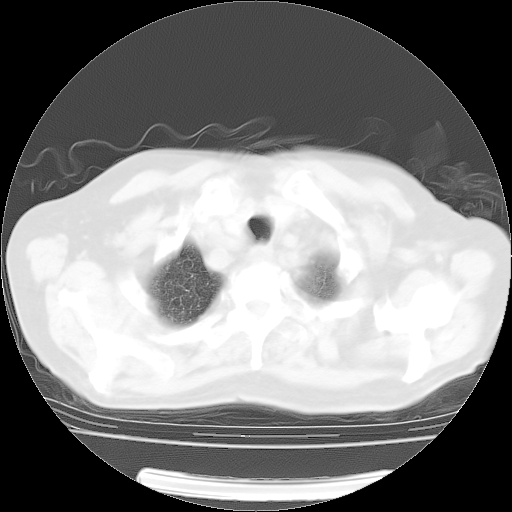

肺部CT平扫未见异常。